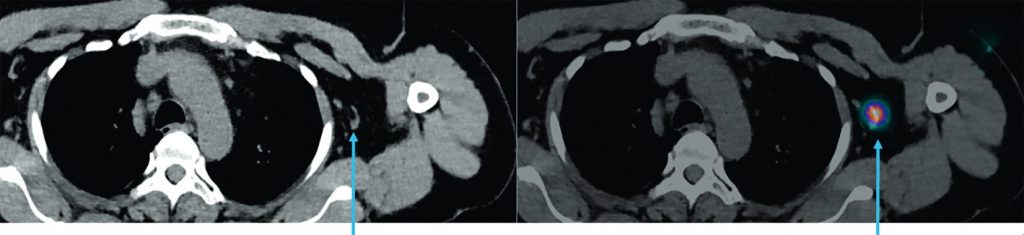

La lymphoscintigraphie aux colloïdes technétiés en préopératoire, pour la recherche de nœuds lymphatiques (« ganglions sentinelles »), est indiquée pour les mélanomes avec un indice de Breslow ≥ 0,8 mm (figure 44.2).

Fig. 44.2. Images axiales TDM et TEMP-TDM d’une lymphoscintigraphie aux colloïdes technétiés. Lymphoscintigraphie réalisée chez une patiente, la veille de la reprise de la cicatrice d’exérèse d’un mélanome avec recherche du ganglion sentinelle. Mise en évidence d’un ganglion sentinelle axillaire gauche (fléche bleue).

Source : CERF, CNEBMN, 2022.